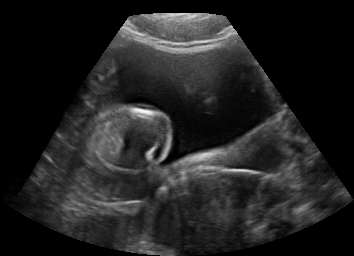

Real in-vivo images. 22 ultrasound sequences were collected using a GE Voluson E8 machine during standard fetal screening exams of 8 patients. Each sequence is several seconds long. We extracted all 4427 frames and resize them to , see Fig. 2 for some examples. The resulting image set was randomly split into training-validation-test sets by a 80-10-10% ratio.